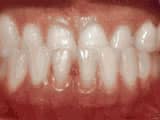

Open bite: front teeth don’t touch

Before

AfterThis girl sucked her thumb as a young child. She started treatment at age 13. She had braces and a special appliance — called a crib — to retrain the tongue, for 28 months. Now she can bite the lettuce out of a sandwich.